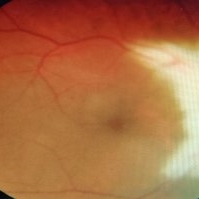

Myelinated Nerve Fiber

May 5 2021 by Priya Rasipuram Chandrasekaran, MBBS, DO, DNB, FRCS

A 31-year-old male presented with a decreased vision of 20/125 N24 with -6.50 DS/-3.50 cyl 90 in the left eye. Fundus examination revealed peripapillary MNF progressing superiorly, obscuring disc and vessels and sparing the macula. OCT of ONH showed hyper reflective NFL and an abrupt ending of RPE and inner retinal layers (IRL) with underlying shadowing at the beginning of hyper reflectivity. The absence of photoreceptor integrity line (PIL) in the macula is believed to cause refractory amblyopia in such patients.

Condition/keywords: myelinated nerve fibers